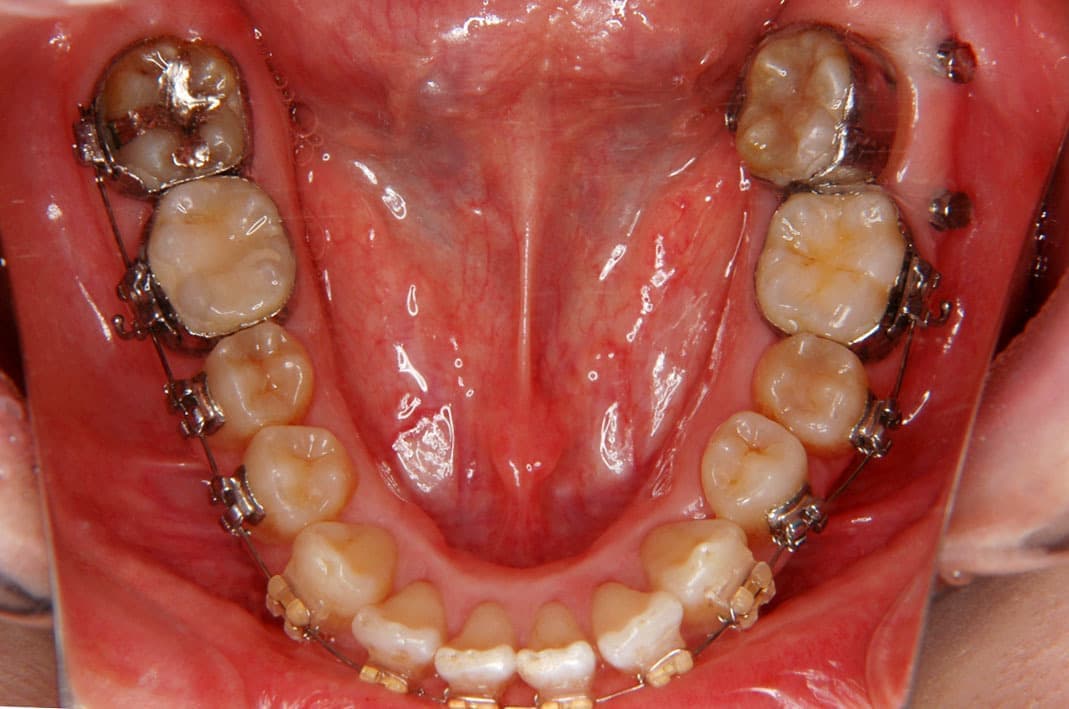

例2)

➡︎